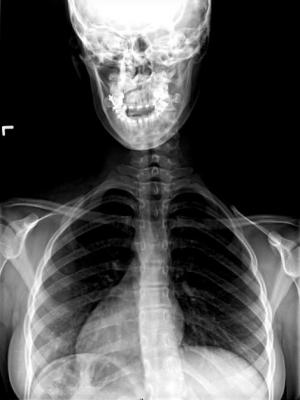

At Shriners Hospitals for Children, 10,000-12,000 radiological images are taken each year of its 6,000 active patients. More than 40 percent of the X-rays taken are of children's spines for diagnosis of conditions like scoliosis and other spinal deformities. Patients with scoliosis typically undergo imaging every three to six months over a period of several years, which can amount to more than 20 total scans over the course of treatment[i]. The EOS system provides high-quality, radiographic images of the patient's skeleton while delivering a radiation dose up to nine times less than a conventional radiography X-ray[ii] and up to 20 times less than a CT scan[iii]. This low dose makes the system of particular value for pediatric patients, especially children who need to be imaged frequently to monitor disease progression such as those with scoliosis.

The EOS system is also the only 3-D, full-body technology capable of scanning patients in a weight bearing standing or sitting position to capture natural posture and joint orientation. This is especially important if a patient uses a wheelchair or other supportive device. Research has demonstrated an intricate relationship between regions of the musculoskeletal system, particularly between the spine and lower body, and 3-D bony images of the skeleton enable physicians to make more informed diagnosis and treatment decisions. Without EOS, clinicians often have to "stitch" together multiple smaller, 2-D images to approximate a full picture of the targeted anatomy. This process is particularly problematic for complex orthopedic conditions such as spinal disorders.